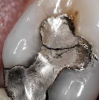

Fig 5. Intra-oral photography. Lower lingual anterior gingiva (Fig 5). Old restoration (Fig 6).

Fig 6. Intra-oral photography. Lower lingual anterior gingiva (Fig 5). Old restoration (Fig 6).

Intra-oral photography. Many dental conditions involve the margins between the natural tooth and the old restoration, which can be difficult to adequately capture with either traditional radi- ography or extra-oral photography. Every operatory should therefore be equipped with a high-quality intra-oral camera; sharing such photographs with the patient during the consultation is quite helpful in explaining the need for longer-term restorations. A well-trained dental hygienist or assistant can quickly  and seamlessly integrate several intraoral photographs during the new patient interview (Figure 5 and Figure 6), discussed below.